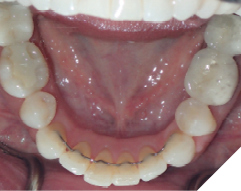

The majority of the orthodontic practices offer a period of “supervised retention” to their patients and communicates the customized retention recommendation with the patient’s general dentists. It is extremely important to work as a team to achieve long term clinical success in maintaining a functional bite and aesthetic smile. The general dentists continue to see their patients on a regular basis and have an opportunity to assess the orthodontic retainers and the bite after the supervised retention period is completed by the orthodontists. With great care, orthodontic retainers would serve for a long time (Fig. 1) without any major issues. However, in some cases, the failure to notice the clinical problems early on results in functional issues that would require a comprehensive orthodontic treatment to correct it (Fig. 2).

Fig. 1A

Fig. 1B

Fig. 1C